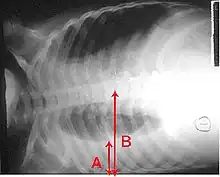

Imaging

A pleural effusion appears as an area of whiteness on a standard posteroanterior chest X-ray.[12] Normally, the space between the visceral pleura and the parietal pleura cannot be seen. A pleural effusion infiltrates the space between these layers. Because the pleural effusion has a density similar to water, it can be seen on radiographs. Since the effusion has greater density than the rest of the lung, it gravitates towards the lower portions of the pleural cavity. The pleural effusion behaves according to basic fluid dynamics, conforming to the shape of pleural space, which is determined by the lung and chest wall. If the pleural space contains both air and fluid, then an air-fluid level that is horizontal will be present, instead of conforming to the lung space.[13] Chest radiographs in the lateral decubitus position (with the patient lying on the side of the pleural effusion) are more sensitive and can detect as little as 50 mL of fluid. Between 250 and 600mL of fluid must be present before upright chest X-rays can detect a pleural effusion (e.g., blunted costophrenic angles).[14]

A pleural effusion as seen on lateral upright chest x-ray- Pleural effusion as seen behind the heart.[17]